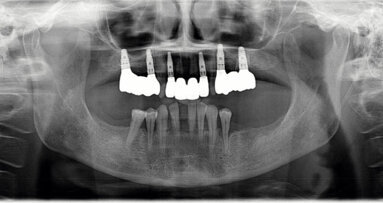

Infekcije su najčešći uzroci upale i bolesti periimplantatnog tkiva, pa čak i gubitka implantata. Prema grubim procjenama, u Njemačkoj se u ustima pacijenata nalazi se oko 25 milijuna implantata. Budući da se periimplantatne bolesti ne javljaju odmah nakon ugradnje, stručnjaci procjenjuju da je trenutačno oko 860 000 implantata zahvaćeno mukozitisom, a 440 000 implantata periimplantitisom. Ovo naglašava važnost sprječavanja infekcija i upala periimplantatnih tkiva.

Dva relativno nedavna sistematizirana pregleda iz 2012. i 2013. pružaju kontroverzne podatke o tome može li i u kojoj mjeri priroda periimplantnog mekog tkiva utjecati na periimplantatne bolesti. Najnoviji pregled s metaanalizom iz 2018., naprotiv, pokazao je pozitivan utjecaj širenja keratinizirane sluznice na zdravlje periimplantatnog tkiva. Zadebljanje mekog tkiva smanjilo je gubitak koštane mase oko implantata. Međutim, autori istraživanja naglašavaju ograničene dokaze svojih rezultata.